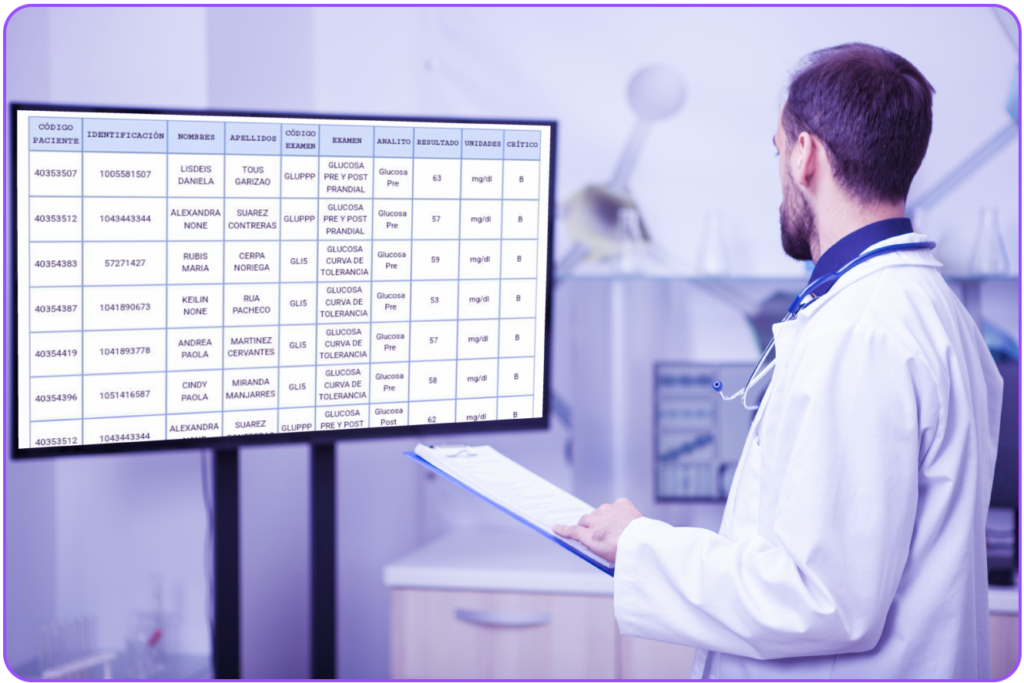

¿Tu laboratorio controla las notificaciones de valores críticos en los resultados de los pacientes?

“La notificación de los valores críticos son de gran importancia para el control y diagnóstico de cada paciente” La herramienta Annarlytics complementa este proceso notificando los valores críticos (Altos o Bajos) detectados vía correo electrónico a los interesados, los cuales son definidos por el cliente. Este proceso se realiza basado en una tarea programada, la […]